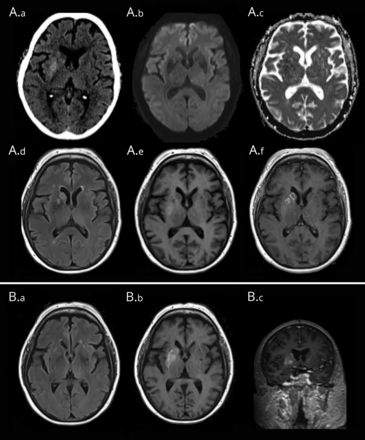

MRI大脑与对比获得入学透露rim-enhancing病变在正确的尾状的头和前方面正确的核不扩散限制但intralesional出血(图)。MRI是重复2个月后,并演示了新的融合性的领域涉及正确的豆状核的T1 hyperintensity保留正确的内囊体积随着失去正确的尾状核头部和分辨率的T2 hyperintensity地区(图)。

(一)初始成像。(一)初始CT: hypoattenuating的外观和微妙的膨胀性的右尾状核头;正确的核巧妙地hyperattenuating。(A.b-A.c)初始扩散:轻度增加信号的fluid-attenuated反转恢复(天赋)hyperintensity跟踪成像与增加扩散系数高表观扩散系数值。(公元)最初的天赋:圆形的区域增加信号包括尾状核头和壳。(A.e-A.f)初始T1前后:hypointense膨胀性的右尾状的头和前壳,它显示了边缘增强。微妙的T1信号增加核的剩余部分。在2个月(B)后续成像。(本科)天赋:解决hyperintensity涉及正确的豆状核。(反方向)T1 precontrast:支流区域涉及正确的基底神经节的T1缩短。 (B.c) T1 postcontrast: T1 shortening, without enhancement, of the caudate head, putamen, and globus pallidus. Interval right caudate head volume loss.